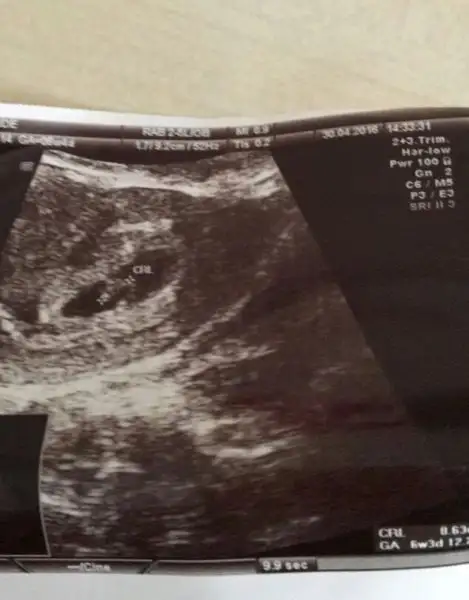

Kizlar benim bebegimede yorum istiyorum :) 8+1